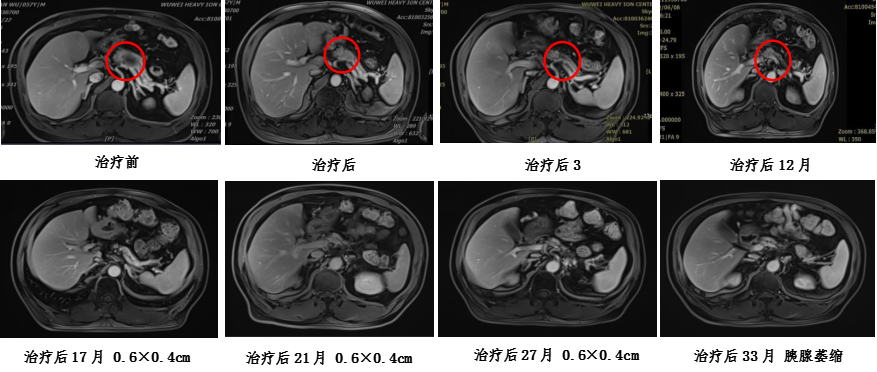

Treatment plan: Carbon ion radiotherapy for pancreatic cancer, supine position with three-field irradiation, total dose: 41.4GyE, 4.6GyE/fraction; prone position PTVboost for local boost dose of 18.4GyE/4 fractions, 4.6GyE/fraction, total prescription dose: PTV 59.8GyE/13 fractions. During treatment, combined with intravenous injection of Nimotuzumab 400mg on day 1 weekly + Gemcitabine 2.0g on days 1 and 8 for chemotherapy. The treatment process proceeded smoothly without significant adverse reactions. Follow-up abdominal MRI after treatment showed a reduction in the pancreatic lesion, with treatment response assessed as partial response (PR).

Carbon ion treatment plan dose distribution map and efficacy evaluation: